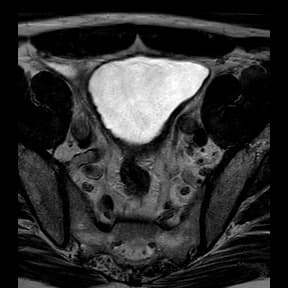

PI-RADS 4 lesion

Cervical carcinoma - stage IIIC1